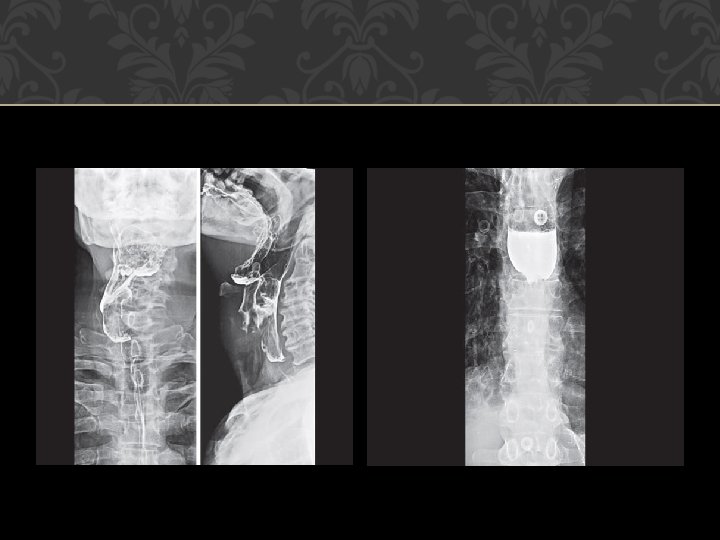

X-ray neck lateral and frontal projections: For cervical osteophytes, lesions of post-cricoid or retropharyngeal region. a. Useful in children. b. Shows radiopaque foreign bodies. c. Saying “e” during exposure brings the tongue anterior, and shows oropharynx better. d. Blowing through closed mouth distends hypopharynx.

Schatzki’s ring Esophageal web

Parapharyngeal mass Achalasia cardia